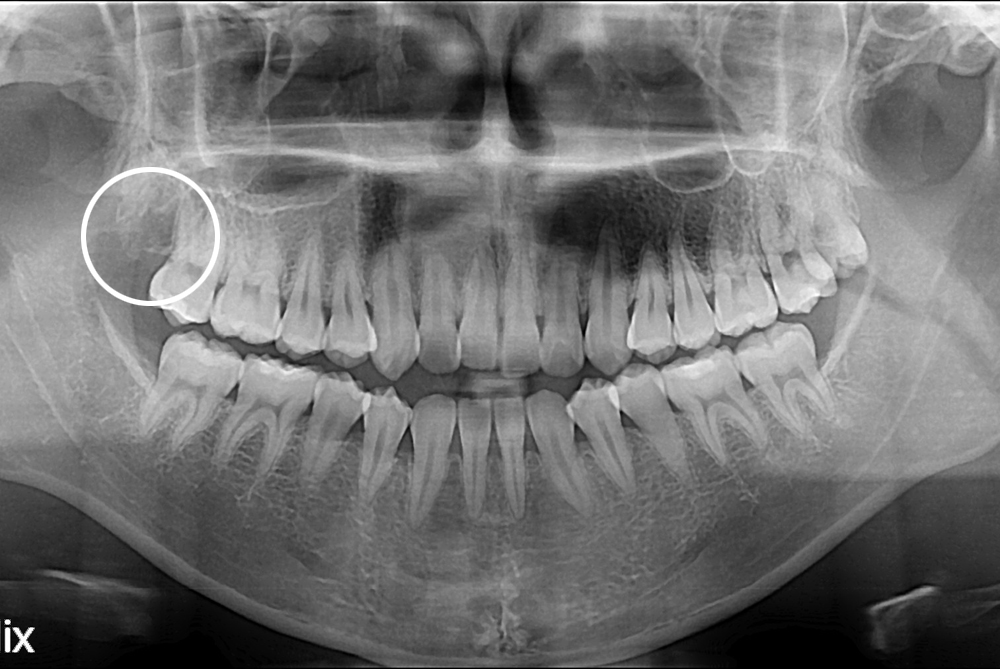

치료사례

세종치과의 진심 어린 치료는 결과로 말합니다.

실제 내원하신 환자분들의 치료 전·후 사례를 확인해보세요.

모든 치료사례 전후사진은 환자분의 동의하에 촬영되었습니다.

모든사진은 동일 환자분의 전후모습을 촬영하였으며, 사진의 밝기조절 외에 임의 수정이 없음을 알려드립니다.